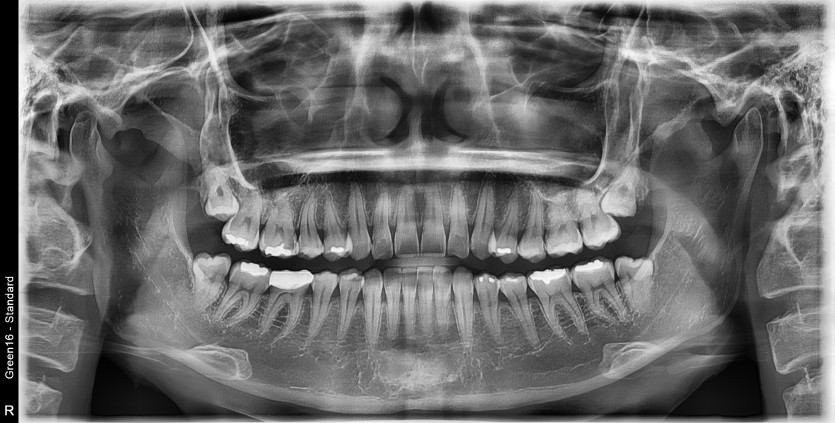

#18,28,38,48 사랑니 발치

구강 외과 전문의가 당일 발치했습니다.